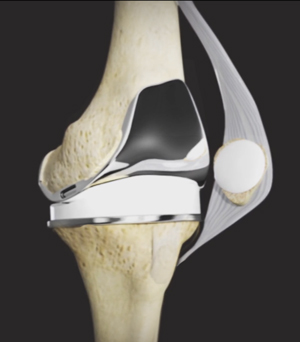

Robotic-Assisted Knee Replacement

What is Arthritis? The knee is made up of the femur (thighbone), the tibia (shinbone) and patella (kneecap). The two menisci, the …

Mako Robotic Assisted Knee Replacement

We understand that making sure you know what to expect from your joint replacement experience is important to you. As you are …